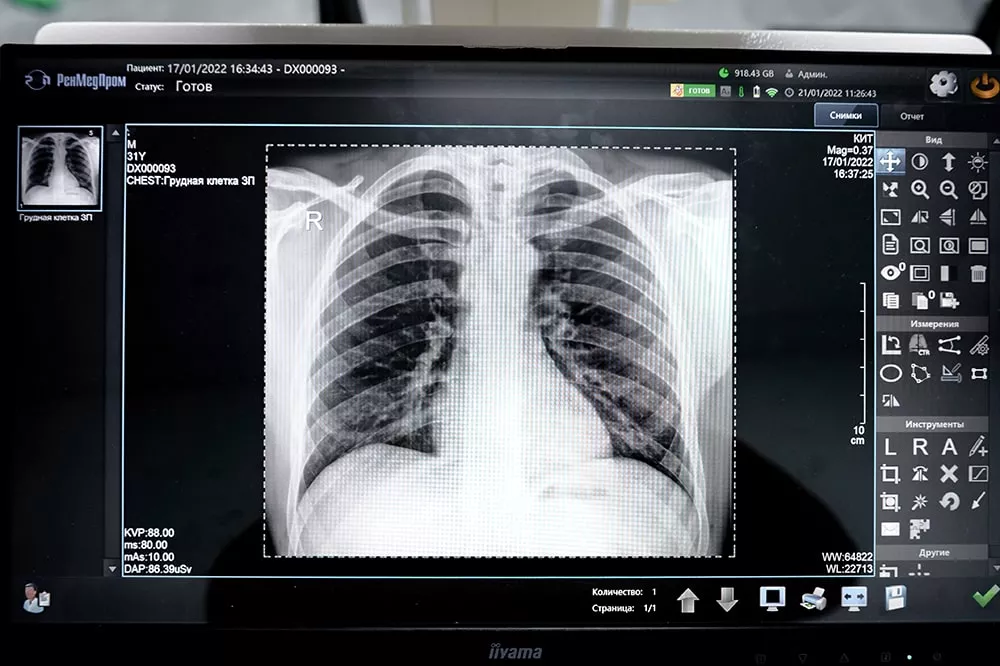

Рентгенография – это популярный метод диагностики, открытый немецким физиком Вильгельмом Рентгеном в 1895 году. Метод основан на уникальном свойстве электромагнитных волн проникать сквозь органы и ткани человека. Просвечивая тело, рентгеновские лучи теряют свою интенсивность. Степень их ослабления зависит от плотности и структуры ткани, через которую они проходят. Это позволяет получить на фотопластине различные изображения, оценить состояние костной ткани, внутренних органов, определить наличие в организме новообразований и посторонних предметов.

- рентген лёгких

- болезни органов дыхания

В зависимости от области исследования рентген может проводиться в положении стоя, сидя или лёжа. Врач-рентгенолог находится в соседнем помещении, откуда он управляет аппаратом и наблюдает за пациентом. Чтобы изображение получилось максимально чётким, в момент выполнения снимка нельзя двигаться, поэтому специалист просит пациента задержать на несколько секунд дыхание. Вся процедура занимает от 5 до 15 минут.

Запись результатов рентгенологического исследования предоставляется на диске. Напечатанный снимок оплачивается отдельно.